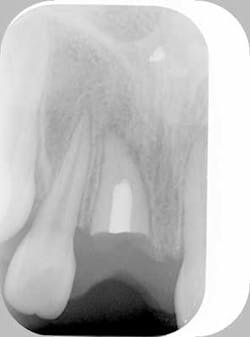

Case study — Traumatized anterior tooth (root submersion case)Fig. 1a: Initial radiograph of a traumatized tooth No. 8 in a female patient too young for dental implants